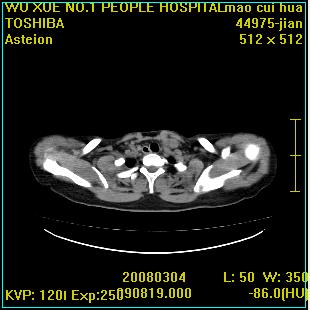

标题: CT12025:男,50岁,左肩活动受限半年。 [打印本页]

标题: CT12025:男,50岁,左肩活动受限半年。

肩关节骨质破坏呈小囊状,其周软组织轻度肿胀,余未见异常。

考虑:肩袖损伤。建议mri。

左侧肱骨头密度不均匀,高低混杂,周围软组织略肿胀,考虑结核性病变。

左侧肱骨头密度不均匀,高低混杂,髓腔密度稍高,周围软组织略肿胀,肌间隙模糊,考虑慢性骨髓炎可能。密切结合临床!